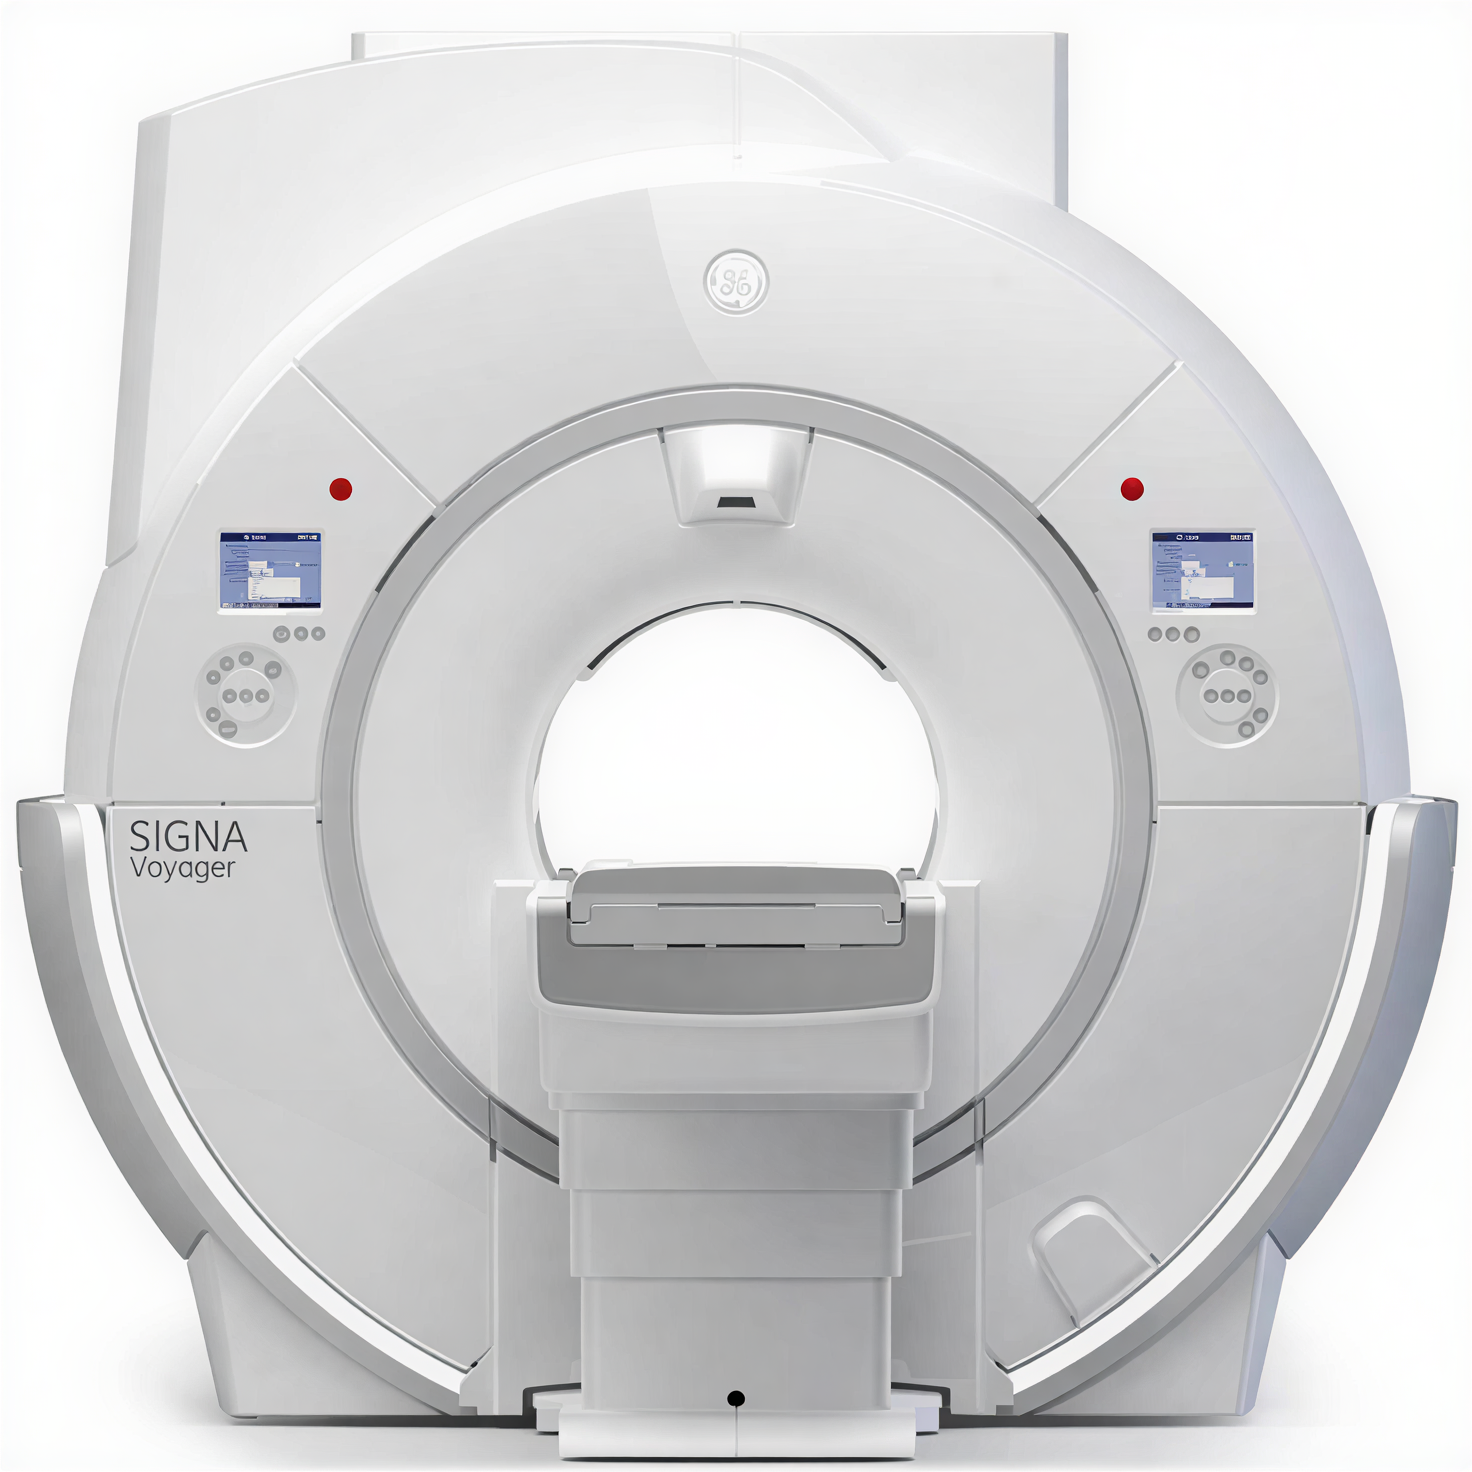

Магнитно-резонансный томограф GE SIGNA Pioneer 3 Тл — премиальная система для продвинутой МР-диагностики

GE SIGNA Pioneer относится к актуальному поколению 3T-систем семейства SIGNA, в которых сделан акцент на сочетании высокой однородности поля, развитой градиентной системы и цифровой архитектуры приёма сигнала. Платформа проектировалась как универсальное решение для нейрорадиологии, онкологии, кардиологии, ортопедии и целотельных исследований. Широкий тоннель и комфортный стол обеспечивают удобство позиционирования пациента и снижают долю прерванных исследований, а развитые средства коррекции движения и шумопонижения (включая технологии Silent и современные алгоритмы реконструкции) помогают получать стабильные диагностические изображения даже у сложных категорий пациентов.

Ключевым преимуществом GE SIGNA Pioneer является использование цифровой архитектуры Total Digital Imaging и современных градиентных модулей с высокой скоростью нарастания, что создаёт основу для продвинутых режимов диффузии, трактографии, функциональных и перфузионных исследований. Интеллектуальные технологии семейства SIGNA Works (нейро-, онко-, кардио- и body-пакеты), а также опции на базе методов глубинного обучения (AIR Recon DL и связанные решения) позволяют одновременно сокращать длительность протоколов и повышать информативность изображений. Интеграция c PACS/RIS по DICOM, поддержка удалённого сервисного мониторинга и возможность поэтапного расширения программного функционала делают систему удобным инструментом для центров, формирующих референсный уровень МР-диагностики и реализующих исследовательские программы.